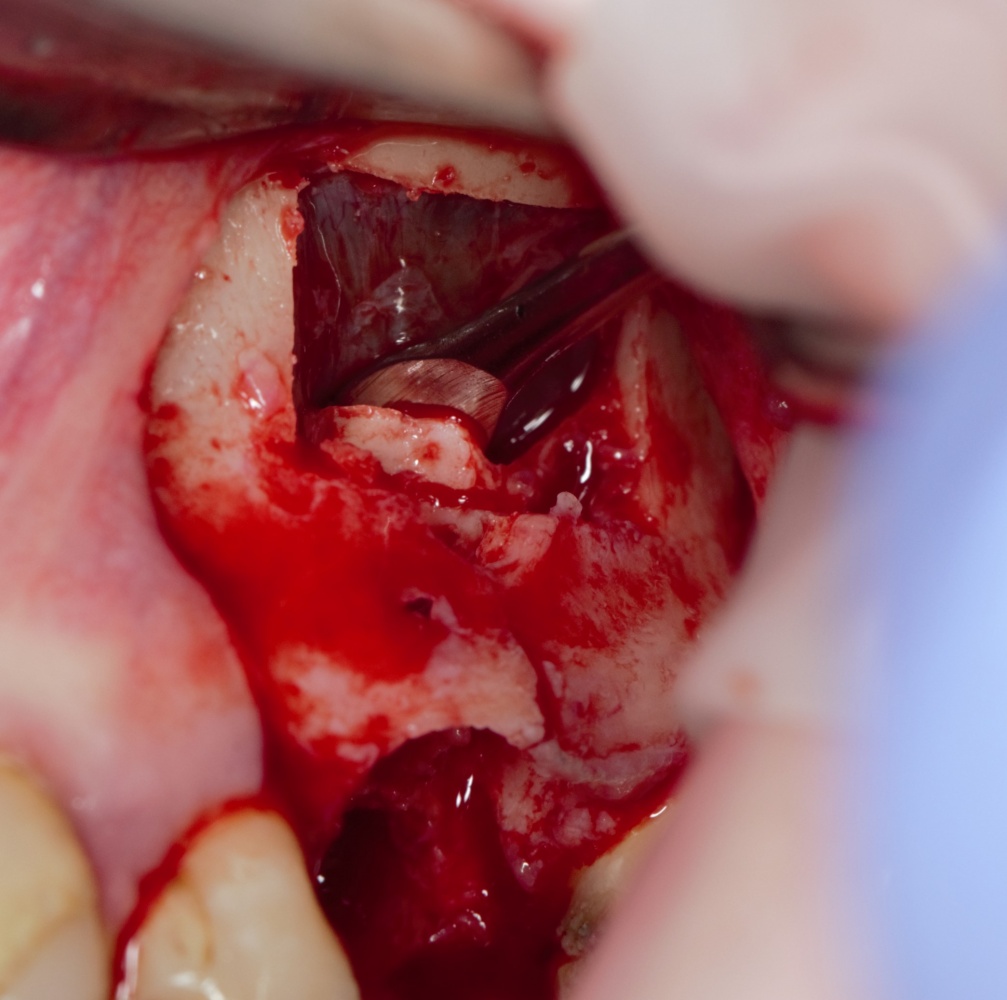

Изоляция области аутографта и имплантатов барьерной мембраной.

Перекрывать костный блок барьерной мембраной или оставить так? По этому вопросу есть много мнений. Между тем, в публикации по методике есть ясное показание, когда это требуется.

Конкретно в этом клиническом случае между костным аутотрансплантатом, ложем и имплантатами есть пустое пространство. Если его не изолировать от мягких тканей, они прорастут и осложнят интеграцию аутографта. Поэтому я решил перекрыть костный блок барьерной мембраной, пусть это делает хирургическую операцию немного дороже.

На этом этапе есть несколько нюансов, о которых я хочу рассказать отдельно.

— я использовал барьерную мембрану Geistlich Bio-Gide, которая имеет две разные поверхности: с одной стороны она рыхлая «адгезивная», с другой — гладкая и прочная. Как укладывать — на результат не влияет, но в плане удобства рыхлую поверхность мы «приклеиваем» к тому, на чем требуется барьерную мембрану удержать. В данном случае хотелось бы удержать её на костной поверхности — следовательно, мы укладываем её рыхлой поверхностью к кости.

Ремарка: примечательно, что во время синуслифтинга ситуация иная - там требуется удержать барьерную мембрану на слизистой оболочке верхнечелюстной пазухи. Следовательно, рыхлая поверхность - на стороне шнайдеровой мембраны.

— много лет мы используем антибиотики для интраоперационной профилактики инфекционно-воспалительных осложнений. Уже в то время мы пришли к выводу, что удобнее всего — порошки антибактериальных препаратов для приготовления раствором: дешевые, стерильные, в удобной упаковке. Прямо в виде порошка их можно добавлять в графт, растворы для ирригации, либо использовать так, как показано на фото. Еще мы используем порошок антибиотика для изготовления пасты, которой обрабатываем имплантаты в процессе ревизии или при лечении периимплантита. Это удобнее и эффективнее, чем интраоперационное использование жидких форм антибактериальных препаратов.

— ты знаешь, что барьерная мембрана может выполнять две функции, каркасную и изолирующую. Первая функция требует обязательной фиксации и натяжения, вторая — нет. В нашем случае «каркасом» регенерата является костный блок, а барьерная мембрана нужна только для изоляции. Поэтому она не требует натяжения и фиксации пинами.

После я внимательно проверил, что костный блок и имплантаты полностью перекрыты. Теперь рану можно ушивать.